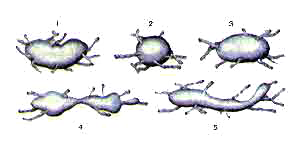

Лимфатические узлы различной формы

1-бобовидная;2-округлая;

3-овоидная;

4-сегментарная;

5-лентовидная.